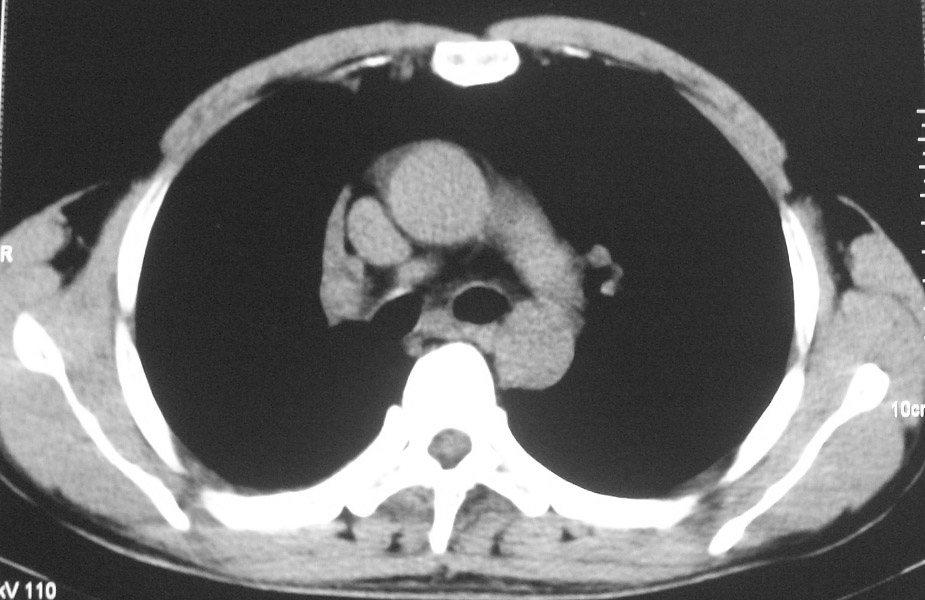

标题: CT5485:[原创]肺部占位请讨论

右上叶支气管肺癌并右上叶阻塞性不张,右侧少量胸腔积液.

右上肺中央性肺癌伴右侧胸腔少量积液!右上肺胸膜下还有一小病灶,不完全排除结核,但个人支持恶性肿瘤!建议早穿刺活检。

右肺上叶中央型肺癌并上叶肺不张、纵隔淋巴结肿大.右侧少量胸腔积液。

右上肺中心型肺癌并肺不张,纵膈淋巴结肿大。右侧少量胸腔积液。

右肺上叶支气管后壁增厚,呈鼠尾状狭窄,纵隔内未见明显增大的淋巴结影,考虑为中央型肺癌伴右上肺不张